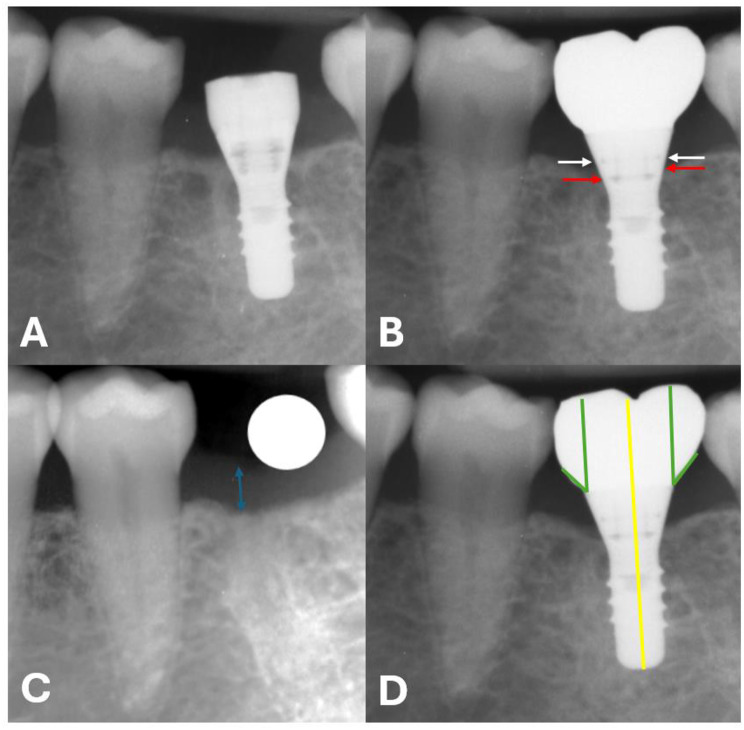

Methods: The University database was reviewed to identify patients treated with tissue-level implants between 2006 and 2020 at the University of Zurich, Switzerland. The study included patients who received screw-retained implant rehabilitations in the posterior area without simultaneous hard- or soft-tissue augmentations and had a follow-up period of at least 12 months. Radiographic measures of marginal bone loss and supracrestal tissue height were conducted using periapical x-rays at different time points. Additional factors analysed included age, gender, smoking status, history of periodontitis, jaw of treatment, type of reconstruction, and prosthetic emergence angle. Associations between marginal bone loss and potential explanatory variables were visualised and analysed. Elastic net regressions were applied to examine potential relationships with marginal bone loss.

Results: A total of 1,479 patients were treated with tissue-level implants. After applying inclusion and exclusion criteria, 106 patients with 106 implants were included in the statistical evaluation after one year (T1, n = 106 implants), and 59 patients with 59 implants were evaluated after three years (T2, n = 59 implants). The mean marginal bone loss was 0.93 mm (SD 0.83) at T1 and 1.04 mm (SD 0.97) at T2. A strong correlation (Spearman) was found between mesial and distal bone loss. Smoking status and the jaw undergoing treatment were associated with bone loss. While these associations were observed in the univariate analysis, a more comprehensive multivariate analysis revealed that these variables had a limited effect on explaining radiographic bone loss.